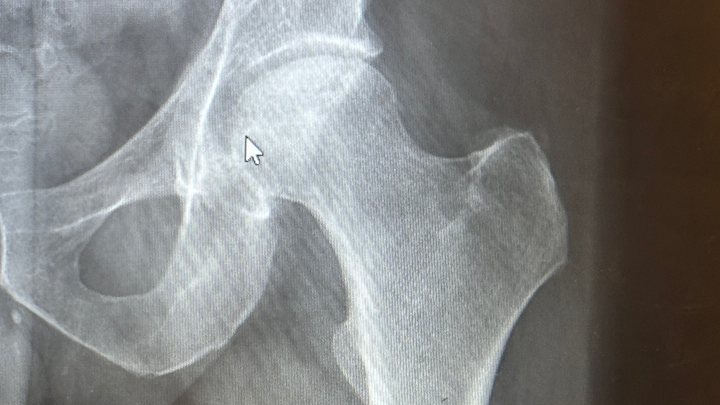

I need help covering the shortfall in income from short-term disability payments after a total hip replacement. This will be my second THR from bilateral avascular necrosis of my femoral heads. My right hip was replaced in February, and the intention had been to wait until next year for my left to be replaced, but it’s not holding up as hoped. I am the sole source of income for our family of five, with my wife staying home with our three children, ages 9, 13, and 15 and homeschooling them. Unfortunately my previous surgery has caused a denial in supplemental short term disability coverage, and the maximum payment is less than $500 a week. That is less than half of what a normal income would be each week.

For those curious, avascular necrosis is the death of bone matter due to restricted or loss of blood flow to a portion of the bone. It is most typically found in long bones like a femur. There is no cure except a hip replacement. Most often it is only diagnosed in the late stages when the pain becomes severe, and when a patient has an X-ray or other scans done. At that stage, the only option is the surgery, with intermittent subcutaneous corticosteroids injections as a layover until surgery can be scheduled.